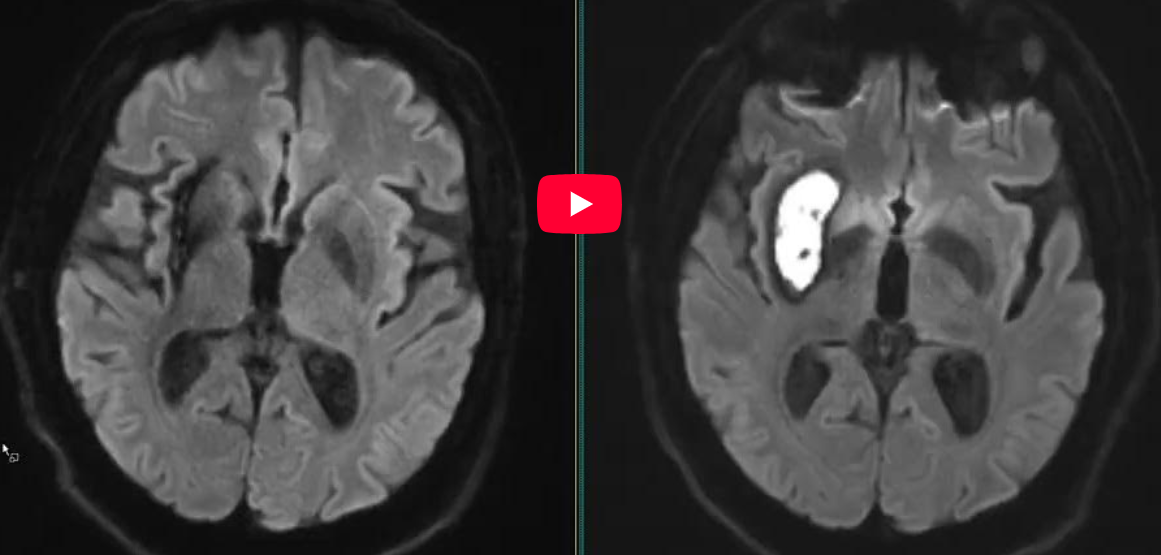

CAZ nr 125: AVC ischemice multiple infra si supratentorial

Video 1: ax FLAIR

Video 2: ax difuzie b800, ax T2, ax SWI ecou de gradient si ax T1 postcontrast

Video 3: coronal b800 si ADC

Video 4: sagital difuzie b800

Discuţie caz nr 125: pacient cunoscut cu patologie oncologică este adus la camera de gardă pentru leziuni neurologice nou apărute. Examinarea IRM cerebrală efectuată nativ și cu substanță de contrast evidențiază multiple leziuni cortico-subcorticale infra și supratentorial în hipersemnal T2 și FLAIR, hiposemnal T1 cu restricție de difuzie a apei, fără priză de contrast – sugestive pentru AVC ischemice acute / subacute.